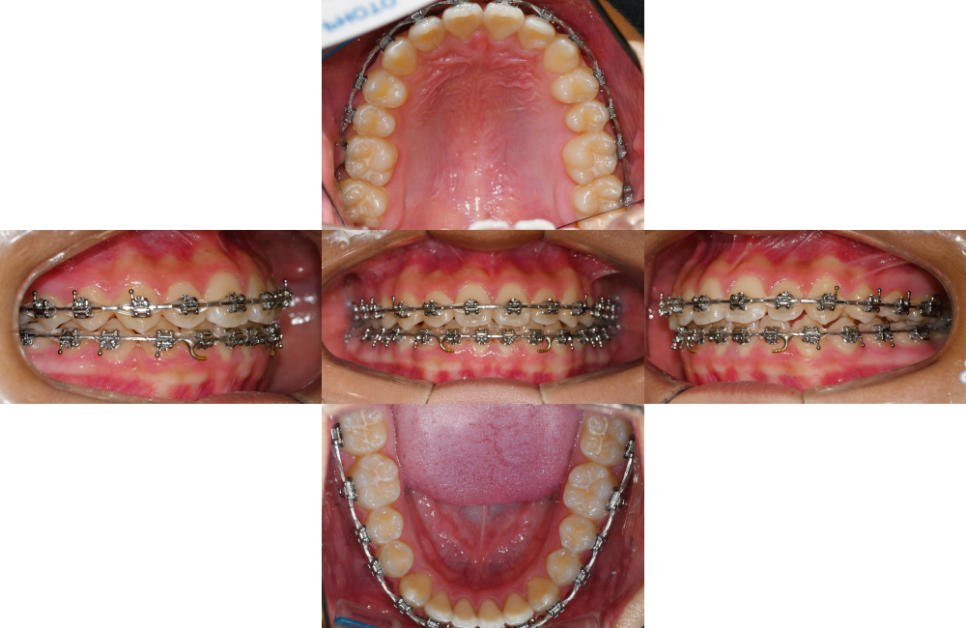

24.02.24

크게 삐뚤거나 배열에서 벗어난 곳이 없다면

이를 뽑지 않고 교정을 진행할 수 있다는 점이

큰 장점인데요.

24.06.22

이동량이 크지 않은 경우라면

예상 치료 기간도 1년 내외로 비교적 짧은 편입니다.

24.11.11

발치를 하지 않고도 충분한 공간을 확보하여

치아들을 올바른 위치로 배열할 수 있습니다.

이 과정에서 위아래 어금니의 교합도

같이 개선되어 기능적인 면에서도

큰 도움이 되는 것이죠.